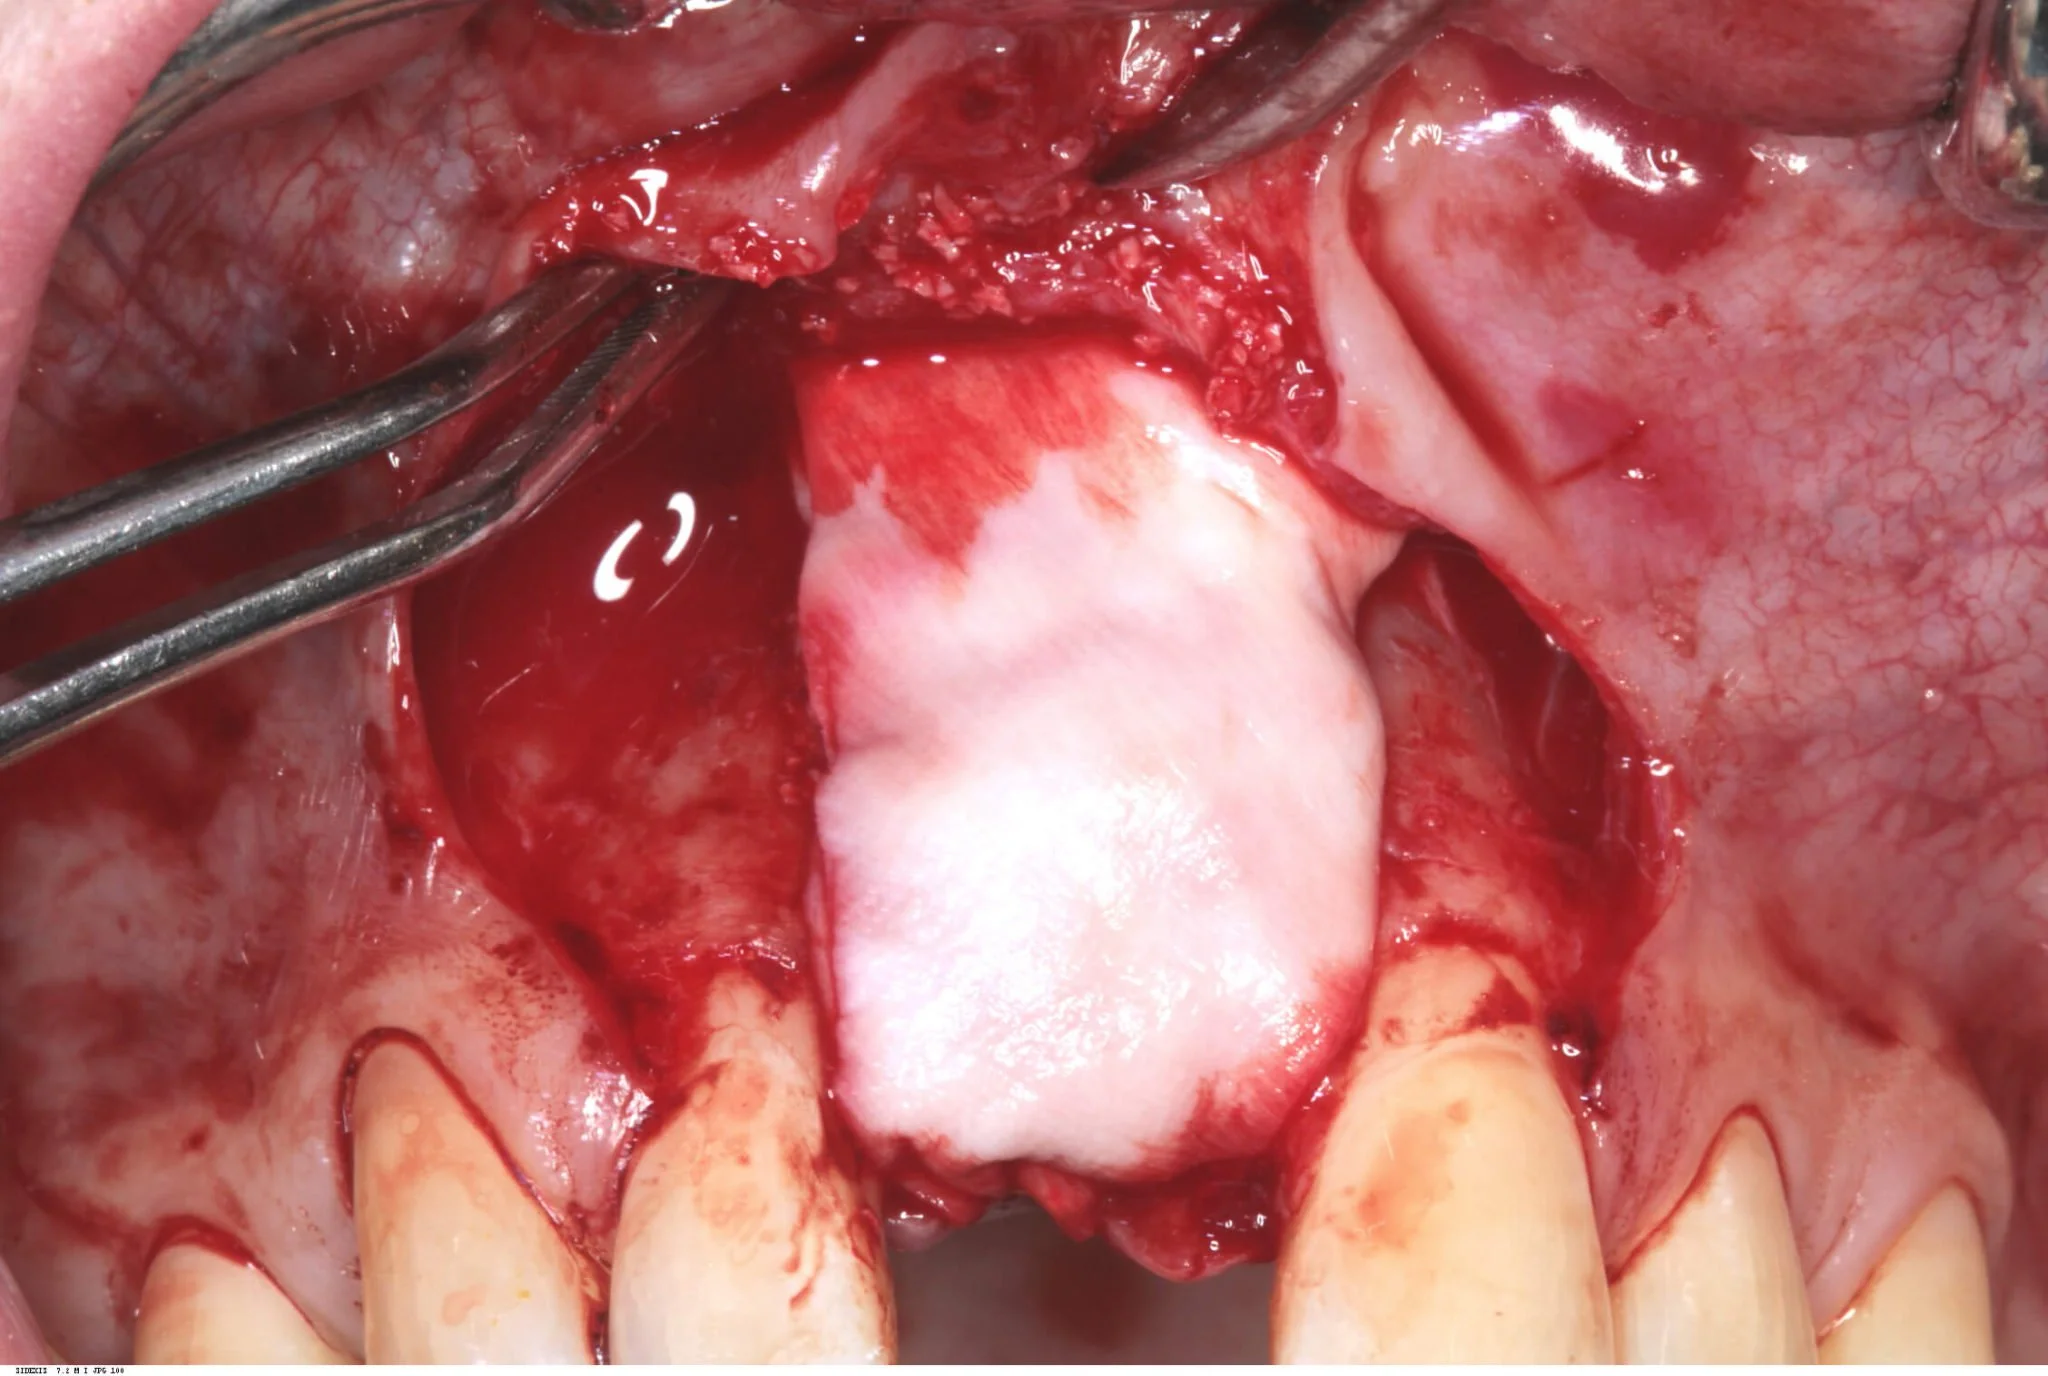

A full thickness flap was raised extending from the distal of 12 to the distal of 21. A Branemark Mark IV implant was placed achieving good primary stability, and the labial plate in the vicinity of the implant perforated to increase blood supply to the planned bone graft.